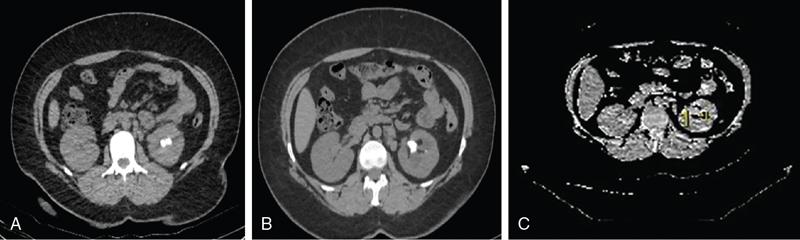

Drushi Patel CONTRAST-ENHANCED ULTRASOUND IN ADULT GENITOURINARY IMAGING Mridula Muthe Ultrasound is the initial screening examination for the evaluation of the renal morphology and suspected renal lesions due to its multiple advantages such as easy accessibility, bedside assessment, affordability and lack of radiation. Vascularity of the kidney and renal lesions can be studied with the use of colour Doppler ultrasound however, it provides information only about the macrovasculature. With the use of microbubble ultrasound contrast agents (UCAs) macro as well as the microvasculature can be studied. Contrast-enhanced ultrasonography (CEUS) is also more sensitive than Doppler ultrasound as it is not affected by blood velocity and angle of insonation of the ultrasound beam. In urology, the established applications of CEUS in adults include characterization of cystic lesions and differentiation between pseudotumours and solid lesions. Box 10.23.1.1 provides a list of European Federation of Societies for Ultrasound in Medicine and Biology (EFSUMB) recommended indications of CEUS in renal evaluation. EUROPEAN FEDERATION OF SOCIETIES FOR ULTRASOUND IN MEDICINE AND BIOLOGY (EFSUMB) RECOMMENDED INDICATIONS FOR USE OF UCA IN RENAL EVALUATION Renal ischaemia. Evaluation of solid renal lesions. Differentiation between solid renal lesions and pseudotumours. Characterization of complex cystic masses. Characterisation of indeterminate renal masses. Renal infections. Follow-up of nonsurgical complex masses. To improve lesion visualization in patients undergoing renal tumour ablation under US guidance and to detect residual tumour either immediately or after ablation. Isolated blunt moderate-energy renal trauma. Follow-up of trauma patients managed conservatively. Characterization of thrombus in renal vein and inferior vena cava. In patients with contraindications for CT- and MRI-based contrast media. Evaluation of lesions in transplant kidneys. Evaluation of ischaemia and vascular complications in transplant kidneys. Tumour response assessment to biologic therapy. Intracavitary CEUS for guiding percutaneous nephrostomy. Source: P.S. Sidhu, V. Cantisani, C.F. Dietrich, O.H. Gilja, A. Saftoiu, E. Bartels, et al., The EFSUMB guidelines and recommendations for the clinical practice of contrast-enhanced ultrasound (CEUS) in non-hepatic applications: update 2017 (long version). Ultraschall in der Medizin-Eur. J. Ultrasound 39 (02) (2018) e2–e44. CEUS involves the intravenous injection of UCAs consisting of gas microbubbles. These UCAs remain purely in the intravascular compartment as they are small enough to avoid filtration by the lungs and too large to enter the interstitial compartment. UCAs cause marked amplification of signals from the flowing blood, thus providing information about the microvasculature and parenchymal perfusion. Sonovue is a second-generation UCA and is the only UCA available in India. It consists of sulphur hexafluoride gas which is exhaled by the lungs and is surrounded by phospholipid monolayer which is metabolised by the liver, making it safe for patients with renal insufficiency. For renal evaluation, a dose of 1–1.5 mL of Sonovue is administered as a bolus dose followed by a 10 mL saline flush. CEUS is performed on machines with contrast-specific software’s using a low mechanical index (MI) technique. The use of a dual image display is beneficial for the evaluation of small lesions. A conventional B-mode ultrasound is first performed to acquire measurements, assess morphology and to detect focal lesions along with Doppler ultrasound to assess vasculature. However, due to limitations in the assessment of focal lesions, microvasculature, complex cysts, poor contrast between the lesion and cortex or medulla, it is preferable to perform a CEUS study for additional characterization. The enhancement pattern of the kidney is different than that of the liver due to the dual blood supply of the liver as opposed to afferent arterial supply and efferent venous drainage of the kidney. After an intravenous bolus of UCA, kidneys show intense enhancement. Contrast is first seen in the main renal artery, followed by its branches. CEUS has only two enhancement phases, that is cortical phase which lasts for 15–30 seconds and a parenchymal phase (enhancement of both cortex and medulla) for 25 seconds–4 minutes after UCA administration. The renal cortex enhances first, followed by the outer medulla which is followed by gradual enhancement of the pyramids (Fig. 10.23.1.1). During the washout phase first, there is a reduction in the medullary enhancement followed by a slower washout of the cortex. As kidneys don’t excrete UCAs, there is no opacification of the pelvicalyceal system. UCAs can act as a problem-solving tool in patients with renal failure as they are not nephrotoxic. Due to its excellent ability to depict renal vascularization, it can be used for detecting perfusion abnormalities. CEUS is useful for detecting vascular causes of renal function deterioration. Renal infarcts appear as wedge-shaped nonenhancing areas in all phases. Renal infarcts show a focal complete lack of parenchymal enhancement on CEUS whereas ischaemic areas show reduced enhancement. CEUS can confidently differentiate infarction from cortical necrosis by the demonstration of preserved hilar vascularity in the latter. Renal pseudotumours such as foetal lobulations, dromedary hump, parenchymal hypertrophy due to renal scarring and column of Bertini can be accurately differentiated from true tumours using CEUS. Pseudotumours show similar enhancement to the adjacent parenchyma and appear isoechoic on all phases while true tumours show different enhancement pattern on at least one phase (Fig. 10.23.1.2). True tumours will cause mass effect and distort the normal vascular architecture of the renal parenchyma whereas in pseudotumours the vascular architecture is preserved. In addition, the identification of medullary pyramids within the mass points towards it being a pseudotumour rather than a true mass. Cysts can be categorized according to the Bosniak classification using CEUS. Due to its superior spatial and temporal resolution, CEUS is considered superior to CT for detecting additional septations, wall or septal thickening and solid components (Figs 10.23.1.3–10.23.1.5). CEUS allows for real-time imaging of blood flow within the septae, wall or nodules within the cysts which may not be seen on CT or MR imaging. The sensitivity of CEUS is comparable to CT for the classification of renal cystic lesions as benign or malignant however, it is not as useful for staging. The follow-up of inoperable complex cystic lesions is better performed with CEUS rather than CT due to the absence of ionizing radiation. Complex cysts or masses with calcifications are not suitable for evaluation with CEUS. CEUS allows a detailed evaluation of the circulation in mass lesions as it demonstrates the macro as well as microvascular enhancement patterns. CEUS has more sensitivity than CT for detecting blood flow in hypovascular lesions. It can also be used to distinguish between complex cysts and solid lesions which remain equivocal on CT and ultrasound (B-mode and colour Doppler). CEUS is sensitive in identifying cystic areas, necrosis, debris and haemorrhage in small tumours that may be difficult to visualize on CECT and MR. Isoechoic lesions on conventional ultrasound are better characterized by CEUS (Fig. 10.23.1.6). Hyperdense renal lesions on noncontrast CT (NCCT) with HU values between 20 and 70 are better evaluated by CEUS which can classify these lesions as solid or cystic. CEUS can suggest the histological subtype of tumours. Clear cell carcinomas show heterogeneous hyperenhancement in the cortical phase and rapid washout along with a peripheral enhancing rim or pseudocapsule seen during the parenchymal phase. Papillary carcinoma shows progressive heterogeneous enhancement during the cortical phase and displays hypoenhancement as compared to the cortex on all phases. Malignant renal vein thrombus will show enhancement as compared to bland thrombus on CEUS. Tumours that are smaller than 3 cm commonly show homogeneous enhancement, regardless of their histologic subtype. Differentiation between angiomyolipoma, renal cell carcinoma and oncocytoma is not always possible. Although, CEUS has excellent sensitivity for the detection of malignancy, it has a higher false-positive rate as compared to CECT. Hence, combined use of CEUS for its high sensitivity and CECT for its high specificity may be performed for an accurate diagnosis. CEUS is effective in patients with complicated pyelonephritis, for identifying inflammatory parenchymal involvement, characterized by round or wedge-shaped hypovascular parenchymal areas, most conspicuous during the late parenchymal enhancement phase. An abscess is seen as a nonenhancing area, with or without peripheral or septal enhancement. CEUS can also be used for the follow-up of renal abscesses. All the aforementioned indications of CEUS in native kidneys also apply to renal transplants. Infarction, vascular complications such as arterial and venous thrombosis can be detected. Quantitative CEUS for assessment of graft dysfunction is a subject of active research. CEUS can be used as an alternative to CT especially in children with isolated blunt moderate energy injuries who are hemodynamically stable. It can also be used in the follow-up of conservatively managed trauma patients and in renal impairment. During Focused Assessment with Sonography for Trauma (FAST), the examination should begin with the kidneys as they have a fleeting enhancement. The kidneys are studied in the arterial phase with two separate doses administered for either kidney during FAST. On CEUS, lacerations, hematomas, and infarcts are seen as nonenhancing areas on late-phase images whereas contusions may show faint enhancement. Pseudoaneurysms and active bleeding are diagnosed on the arterial phase. Crucial complications such as devascularized parenchyma and acute cortical necrosis can also be diagnosed on CEUS. Pelvicalyceal system injury cannot be detected by CEUS as UCAs are not excreted by the kidneys. CEUS can be performed in conjunction with percutaneous ablation therapies. Preablation evaluation with CEUS is essential to assess lesion vascularity and to compare pre and postprocedure tumour viability. Also, the identification of a pseudocapsule predicts improved ablation efficacy. CEUS has demonstrated high sensitivity, specificity and accuracy for the early detection of residual unablated tumour. Dynamic contrast-enhanced ultrasound is a useful tool for early identification of responders and nonresponders, enabling tailoring of the treatment regimen. It is performed by two methods – Bolus injection of a UCA with time-intensity curve analysis (commonly used) and intravenous injection of UCA with disruption–replenishment analysis. In patients with chronic kidney disease, the contrast enhancement is less intense and fades earlier as compared to a normal kidney. CEUS aids in characterizing renal lesions in patients with renal failure. Characterization of lesions with indeterminate appearances in patients with renal dysfunction, on conventional US prevents unnecessary further evaluation with contrast-enhanced CT or MRI and further deterioration of the renal function as well as unwarranted investigations. CEUS nephrostomogram can be performed after percutaneous nephrostomography to confirm the correct positioning of its tip, detect the site of obstruction and to diagnose complications. UCAs can be safely administered in patients with minimal risk. They can be safely administered in patients with renal insufficiency as they are not excreted by the kidneys. Prior laboratory tests are not indicated as they are not nephrotoxic and don’t interact with thyroid function. Most adverse effects are mild such as nausea, headache, chest discomfort, chest pain and resolve spontaneously. The contraindications include known hypersensitivity, patients with right-to-left shunts, severe pulmonary arterial hypertension (pulmonary arterial pressure >90 mm Hg), uncontrolled systemic hypertension, and respiratory distress. The rate of anaphylactic reactions is significantly lower than iodinated contrast media and comparable to gadolinium-based contrast agents. Caution should be exercised in patients with severe acute coronary disease and in patients with unstable angina. CEUS is a rapidly evolving technique, can be conveniently performed as an extension of conventional ultrasound and acts as a valuable tool in the characterization of indeterminate renal lesions, especially when the lesion is small. The advantages of CEUS include quick assessment, real-time imaging, high contrast resolution, excellent safety profile, lack of ionizing radiation, great repeatability, and most importantly, ideal for contrast evaluation in patients with deranged renal function. DUAL-ENERGY AND SPECTRAL IMAGING IN GENITOURINARY SYSTEM Aditi Chaitanya Gujarathi-Saraf Dual-energy CT (DECT) also known as ‘spectral imaging’, was first conceptualized in the 1970s. However, the clinical applications of DECT have recently emerged as owing to improvements in postprocessing techniques. The development of a single-detector, single-source DECT (ssDECT) with the capability for rapid alternation between two peak voltage settings (‘fast switching’) and a dual-detector, dual-source DECT (dsDECT) system in last few years have made possible various applications in solving clinical problems. In DECT, the simultaneous use of two different X-ray beam energy settings (80 and 140 kVp) allows the differentiation of materials on the basis of their attenuation characteristics (material density). There are two major applications of DECT in genitourinary system. First being characterization of renal calculi to differentiate those containing uric acid (UA) from those which do not. The other application is to characterize small renal masses which include differentiating complex cysts from renal tumours, detection of solid growth in PCKD patients and detection of residual tumour after thermal ablation of a renal neoplasm. The principle of DECT imaging is based on the differential absorption of X-ray energy at variable kVp settings. In DECT, two energy levels (typically 80 and 140 kVp) are used to acquire images that can be processed to generate additional datasets. Thus, a tissue or any material in the body shows different degrees of attenuation when scanned at different X-ray energies. Conventional CT numbers (attenuation measurements in Hounsfield units) are related to the linear attenuation coefficient of a particular material. The unique linear attenuation coefficients obtained by imaging at two different energies can be used to discriminate between different materials (e.g. fat, calcium, iodine and water). The characterization of material on DECT depends on their CT number ratio (CTR) also called dual-energy ratio. DE RATIO = CT number of a given material in the low-energy image CT number of the same material in the high-energy image DECT and spectral CT can be performed by three techniques (Fig. 10.23.2.1): Two sets of material-specific images are created to detect the presence or absence of a material. The two basic materials selected should have significant difference in mass attenuation coefficients and atomic number. The two commonly selected pairs are: Iodine-specific images are most commonly used in the clinical practice. When iodine is paired with water, two separate image data sets are generated. On water density image, the voxels that show change in attenuation due to presence of iodine are removed. These are instead represented on iodine density images. Thus, virtual unenhanced images are generated which resemble the conventional unenhanced images. Renal calculus disease is a common disease affecting approximately 10%–14% of population in India commonly affecting 31–45-year-old patients. Accurate diagnosis of composition of renal calculi is crucial as the frequency of prevalence and recurrence rate of renal calculi is high in most states of India. The obstructing calculi can lead to obstructive uropathy, pyelonephritis, urinary sepsis with nearly 50% of the patients being affected by renal failure. There are multiple compositions of renal calculi, most common being calcium oxalate (70%), calcium phosphate (20%), uric acid (8%) and cystine (2%). In general, UA calculi have lower attenuation values than nonuric acid calculi (i.e. struvite, cystine and calcium) on conventional CT. However, it may be difficult to distinguish between the two due to overlap in attenuation values. Here DECT becomes a problem-solving tool as it uses the two-material differentiation approach. Thus, in addition to size and location, DECT provides information about the composition of calculi to the urologist. DECT has high sensitivity of 88%–100% and high accuracy of 93%–100% to differentiate UA calculi from nonuric acid UA calculi. This is of utmost clinical importance as UA calculi can be treated medically whereas non-UA calculi require invasive methods of treatment such as extracorporeal shockwave lithotripsy (ESWL) or percutaneous nephrolithotripsy (PCNL). In clinical practice, NCCT scan of KUB region is performed at 80 and 140 kVp to generate two image datasets and obtain the DE ratio. A cut-off value of DE ratio of 1.2 is used to differentiate UA calculi from non-UA calculi (Fig. 10.23.2.2). Following flow chart shows differentiation of renal calculi based on DE ratio.